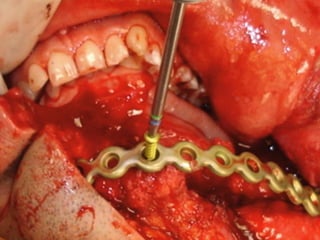

Trismus importante debido a que

El tumor ya rompió el hueso com-

Pacto de la cara interna de la

Mandíbula y empezó a tomar el

Músculo pterigoideo interno y

milohioideo.

Sierra de GigliSierra de Gigli

Luxación de hemimandíbula

Pieza quirúrgica

Plantilla flexible para dar forma previa al implante

Se respetó el cóndilo para anclar la prótesisSe respetó el cóndilo para anclar la prótesis

Límite tumoralLímite tumoral

Area de lisis ósea a nivel de la línea

Miliodes que contracturó los músculos

Milohioideo y pterigoideo interno

Dificultando la deglución y determinando

Trismus importante.

Pieza en proceso de examen por histopatología

Dr. Ismael Espejo Plascencia Patólogo

48 horas de post-operatorio

Maxilectomía parcial